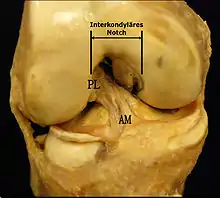

Facteurs de risque intrinsèques

Les facteurs anatomiques sont soupçonnés déjà depuis longtemps. La résistance à la rupture d'un LC dépend directement de sa largeur, qui varie d'un individu à l'autre. Dans une étude anthropométrique, les LCA du genou controlatéral intact de patients victimes d'une rupture de LCA ont été comparés avec ceux d'individus de même poids corporel. Les volumes des LC ont été déterminés par IRM. Dans le groupe des blessés, le volume des LCA contralatéraux était en moyenne 1 921 mm3, tandis que dans le groupe de contrôle, il était de 2 151 mm3. Les auteurs de l'étude en concluent que les différences anthropométriques des volumes – et de la largeur qu'on en déduit – des LC ont une influence directe sur la probabilité d'une rupture de LC sans agression externe[49]. Déjà dans des études précédentes, on a établi une corrélation entre cavité ligamentaire du fémur (notch intercondylaire : voir figure) étroite, liée à des ligaments plus étroits, et un risque plus élevé de rupture de LC[50],[51],[52],[53],[54],[55]. Cependant on n'est pas arrivé à un consensus scientifique, parce que d'autres études aboutissent à des résultats opposés[43],[56],[57]. Par rapport aux hommes, les femmes ont une cavité ligamentaire plus étroite, ce qui pourrait expliquer une incidence plus élevée des ruptures de LC chez les femmes[58],[59].